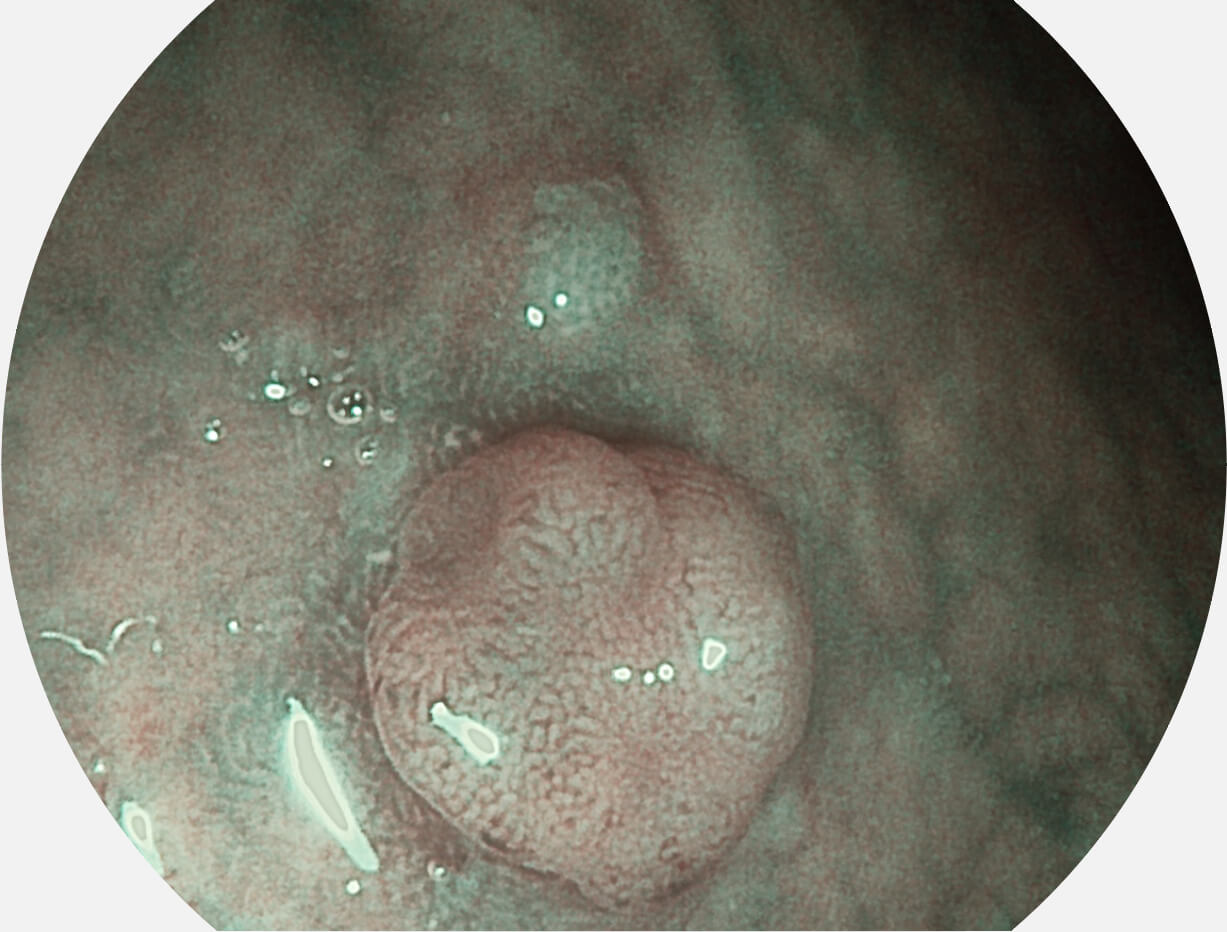

白光图像

SFI图像

Versatile Intelligent Staining Technology, VIST

强调浅层黏膜结构的同时,保证照明亮度和提升浅层微血管与中层血管颜色对比度,病变边界更清晰。